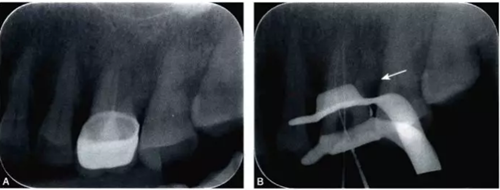

(一)X線診斷

完全鈣化根管在X線片上的表現(xiàn)是根管影像模糊,密度增高,根管密度與周圍的牙本質(zhì)密度接近,甚至無法區(qū)分根管與牙本質(zhì)的影像。有些根管,可表現(xiàn)為根管影像時(shí)斷時(shí)續(xù)或模糊不清,為不完全鈣化根管表現(xiàn)(圖4-1A)。細(xì)小根管的病例在X線片上,根管影像隱約可見,與同名牙或鄰牙相比,根管較為細(xì)小影像清晰度降低。

細(xì)小鈣化根管的根管口,即使是在口腔手術(shù)顯微鏡下,也不容易被發(fā)現(xiàn)。在鈣化根管的早期,鈣化牙本質(zhì)的顏色可能與周圍正常牙本質(zhì)不同,因此,多數(shù)情況下,利用口腔手術(shù)顯微鏡能夠發(fā)現(xiàn)根管所在位置。有的鈣化根管牙本質(zhì)與周圍牙本質(zhì)顏色相似,難以區(qū)分,此時(shí)借助手術(shù)顯微鏡的高倍放大作用,結(jié)合根管解剖知識(shí),仔細(xì)觀察顏色的細(xì)微差異,有助于提高探查根管口的成功率。完全鈣化的根管,表現(xiàn)為均質(zhì)的硬組織結(jié)構(gòu),有時(shí)與正常牙本質(zhì)結(jié)構(gòu)難以區(qū)別,當(dāng)采用各種方法均無法疏通時(shí),為了避免產(chǎn)生新的并發(fā)癥,不宜強(qiáng)行疏通,可定期追蹤觀察(圖4-2)